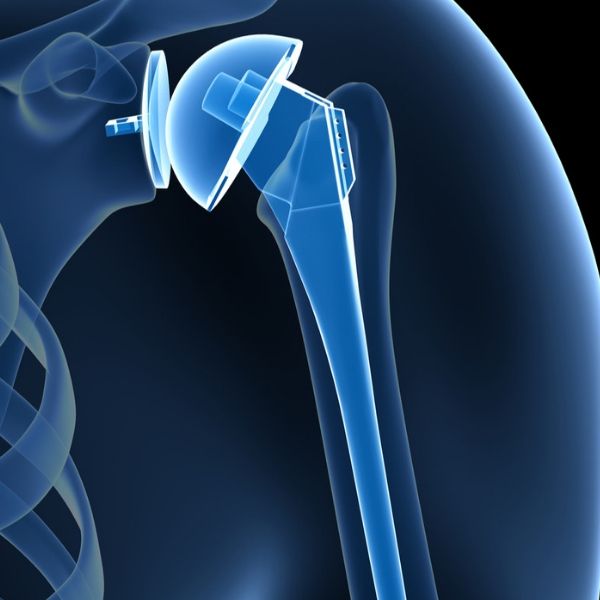

• Χειρουργικής Ώμου και Αγκώνα με έμφαση στην αρθροσκόπηση, την αρθροπλαστική και το τραύμα.

Απέκτησε ειδικό ενδιαφέρον για την χειρουργική Ώμου και Αγκώνα και εξειδικεύτηκε στον τομέα ακολουθώντας αναγνωρισμένα μετεκπαιδευτικά προγράμματα ‘’Clinical Fellowships’’ στο